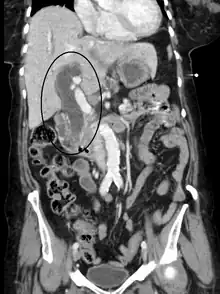

Imaging

Medical imaging such as ultrasound, CT scan, and HIDA scans are useful for detecting bile duct blockage.[12]